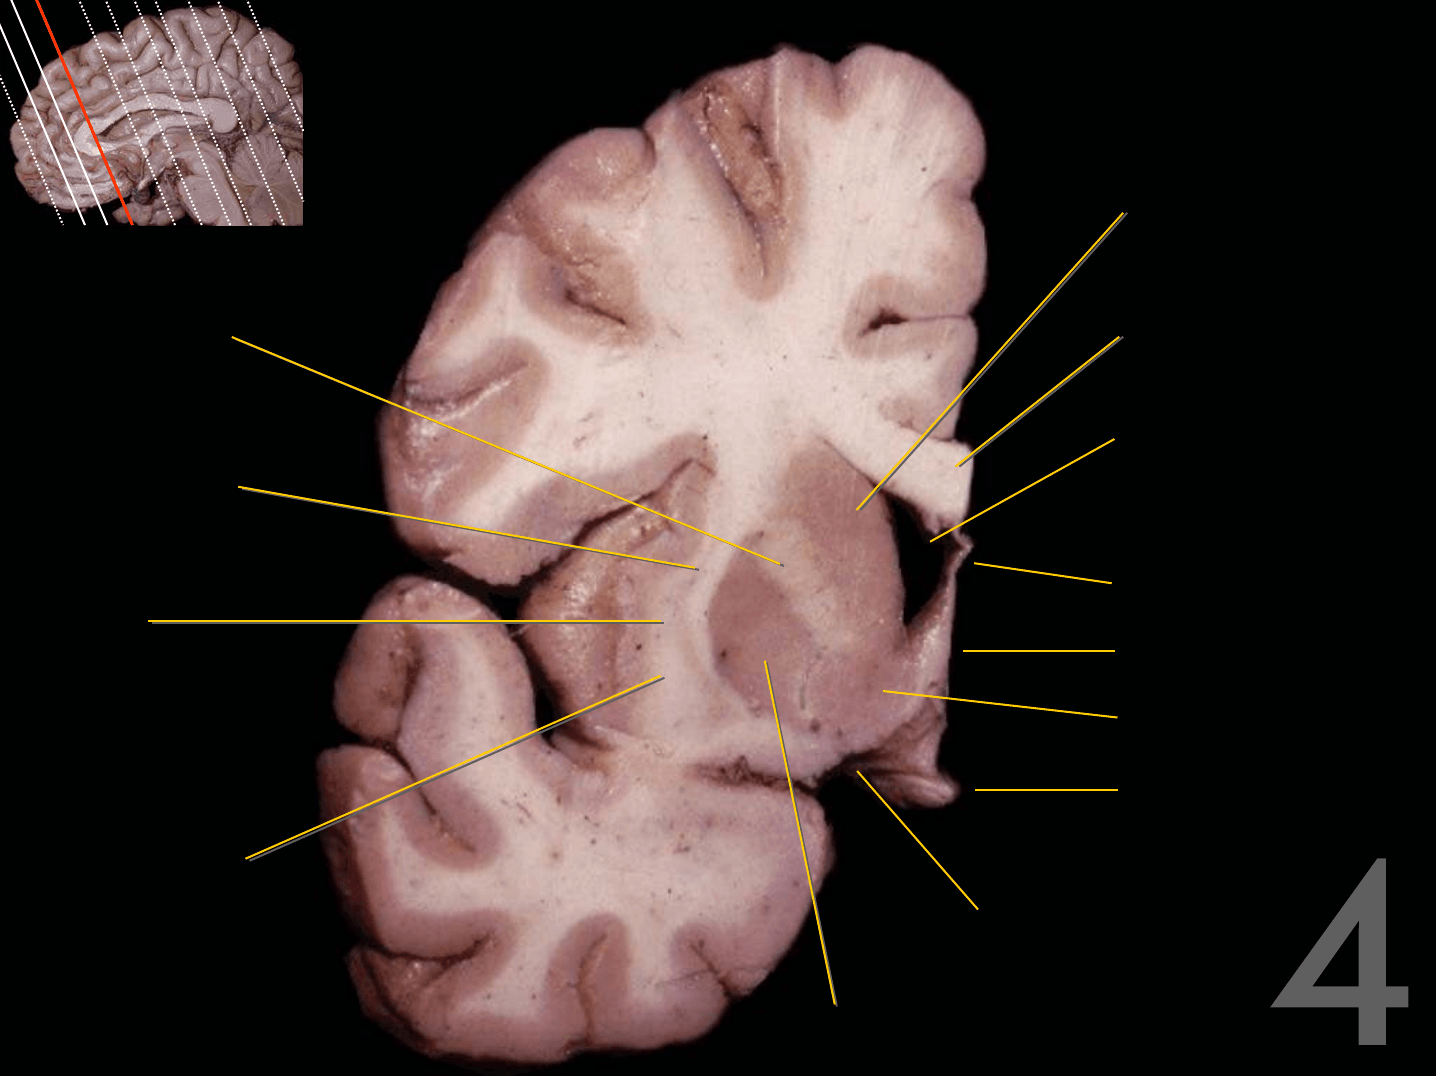

Tronco del cuerpo calloso

Rodilla del cuerpo calloso

Columna del fórnix

Comisura anterior

Foramen interventricular

Infundíbulo

Habénula

Pico del cuerpo calloso

Acueducto del mesencéfalo

Estría medular del tálamo

Adhesión intertalámica

Lámina terminal

Quiasma óptico

Tubérculo mamilar

Comisura posterior

Glándula pineal

Rodete del cuerpo calloso

Calota mesencefálica

Túber cinereum